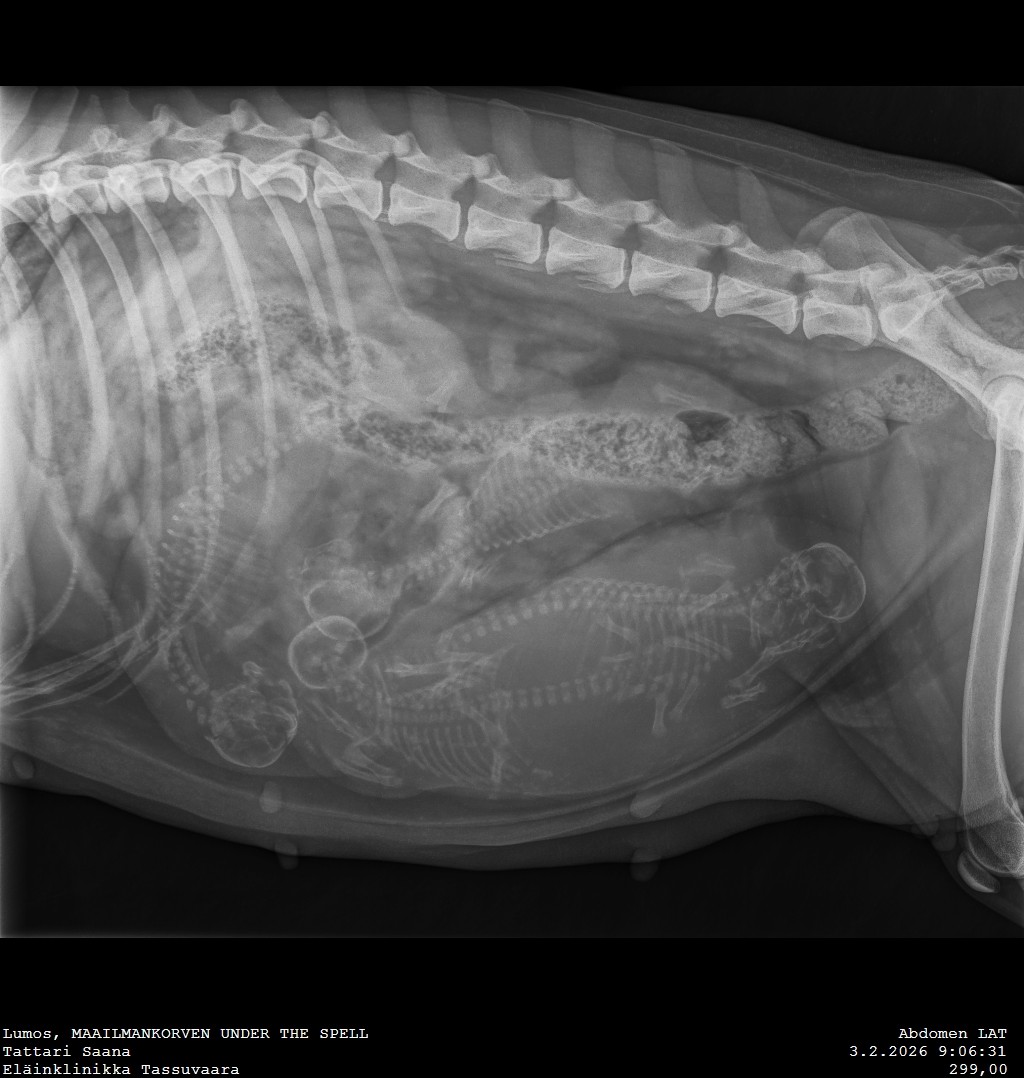

A-pentue aka Daltonin veljekset maailmaan

Huh huh, mistähän sitä edes aloittaa. Vaikka siitä, että kuka ihme antoi meille luvan alkaa kasvattajiksi :D Vitsi, vitsi. Mutta kyllähän tämä vähän käsittämättömältä tuntuu, kun tätä pentuetta on pohdittu, suunniteltu ja toivottu erittäin pitkään. Ja vaikka tätä on suunniteltu pitkään, niin varmaankaan kenellekkään, joka meidät tuntee, ei tule...